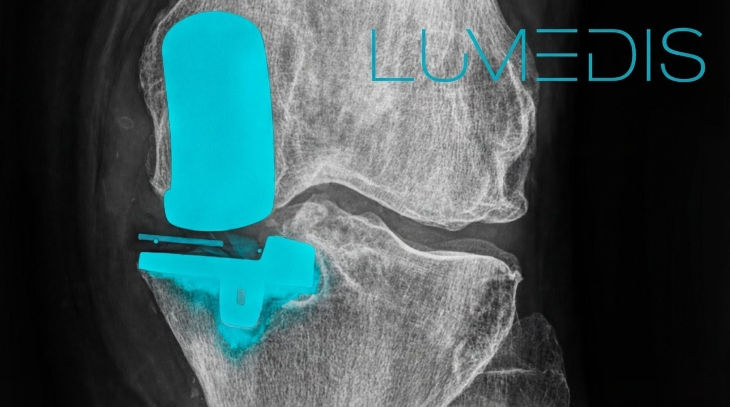

mediale Schlittenprothese (Oxford-Schlittenprothese) - seitliche Röntgenaufnahme

- Oberschenkelknochen (Femur)

- Kniescheibe (Patella)

- Oberschenkelschild des Oberschenkelknochens (mediale Femurkondyle)

- Unterschenkelkomponente der Schlittenprothese

- Schienbein (Tibia)